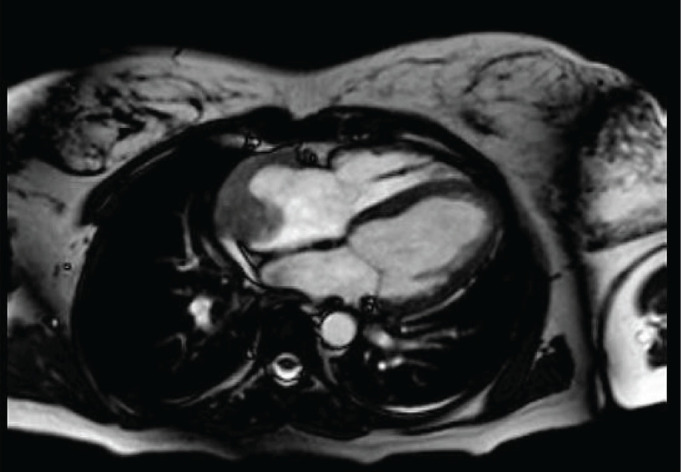

原发性心脏血管肉瘤是一种非常罕见且生长迅速的肿瘤,其中妊娠与原发性心脏血管肉瘤同时发生极为罕见。这使得诊断变得困难,有时甚至很晚,导致从发现的那一刻起预后就很差。我们提出的情况下,38岁的孕妇在妊娠第16周诊断为产科抗磷脂综合征谁来到急诊室虚弱,呼吸困难,心动过速和低血压。经胸超声诊断为心包填塞。她因外源性心源性休克住进重症监护室。经食管超声检查显示右心房有一个大的杂色肿块,提高了心房血栓和心肌肿瘤的鉴别诊断。择期剖宫产于妊娠22周。几个月后,患者因非常不利的临床进展再次入院,经历弥漫性肺泡出血/血管炎,生命支持措施难治性。同意在等待心脏内活检的解剖病理报告时限制治疗努力,随后确认心脏血管肉瘤的组织学性质。本病例报告强调其罕见性,表现出非特异性的临床表现,这使我们认为右心房血栓形成和血管肉瘤的致命预后,主要与由于诊断较晚导致疾病进展有关。

Primary cardiac angiosarcoma is a very rare and fast-growing tumour, where the coincidence of pregnancy and primary cardiac angiosarcoma is extremely rare. This makes diagnosis difficult and sometimes late, resulting in a poor prognosis from the moment of detection. We present the case of a 38-year-old pregnant woman in the 16th week of gestation diagnosed with obstetric antiphospholipid syndrome who came to the emergency department with asthenia, dyspnea, tachycardia and hypotension. A transthoracic ultrasound was performed with a diagnosis of pericardial tamponade. She was admitted to the intensive care unit for extrinsic cardiogenic shock. Transesophageal echography was performed, showing a large variegated mass in the right atrium, raising the differential diagnosis between atrial thrombus and myocardial tumour. Elective cesarean section was performed at 22 weeks of gestation. Months later, the patient was readmitted with a very unfavorable clinical evolution, experiencing diffuse alveolar hemorrhage/vasculitis refractory to life support measures. It was agreed to limit the therapeutic effort while awaiting the anatomopathological report of intracardiac biposia, subsequently confirming the histological nature of cardiac angiosarcoma. This case report highlights its rarity, showing a non-specific clinical presentation, which directed us towards a thrombosis in the right atrium and the fatal prognosis of angiosarcoma, mainly related to the progression of the disease due to a late diagnosis.